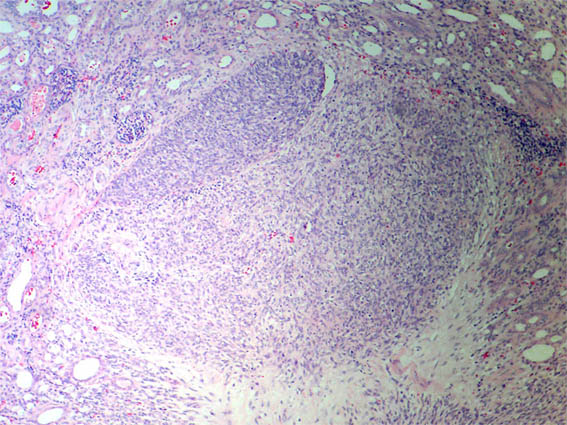

Figure 2. H&E, X100.